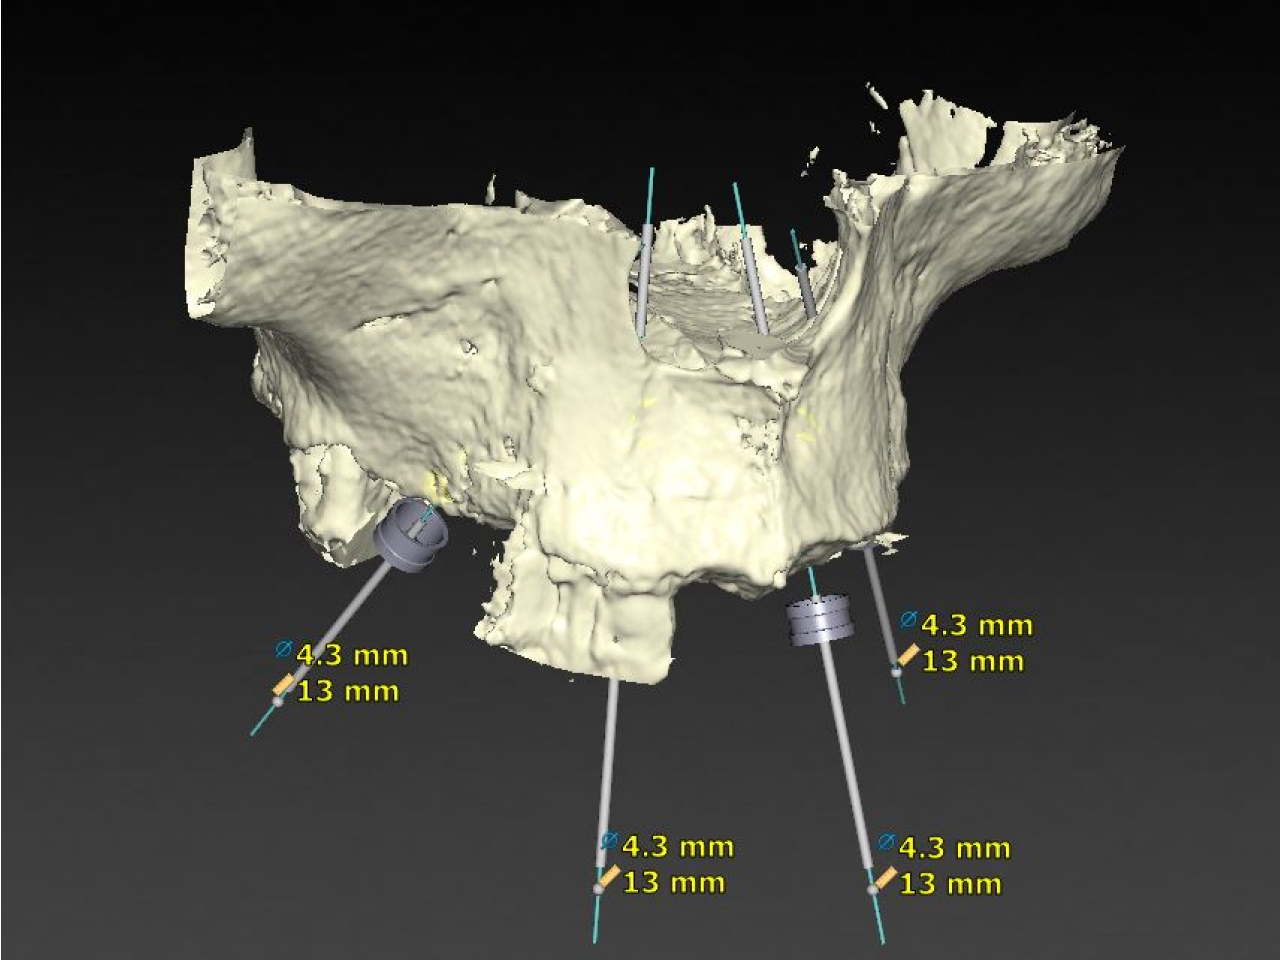

While the ideal position and size of your teeth are designed on specialised ‘bite and smile design’ software, your surgery can be planned on specialised surgical planning software. A CT scan is obtained and loaded into the planning software to allow Dr. Currie to plan the appropriate number and size of dental implants for your surgery.